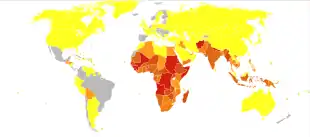

The measles vaccine is effective at preventing the disease, is exceptionally safe, and is often delivered in combination with other vaccines.[7][18] Vaccination resulted in an 80% decrease in deaths from measles between 2000 and 2017, with about 85% of children worldwide having received their first dose as of 2017.[14] Measles affects about 20 million people a year,[3] primarily in the developing areas of Africa and Asia.[7] It is one of the leading vaccine-preventable disease causes of death.[19][20] In 1980, 2.6 million people died from measles,[7] and in 1990, 545,000 died due to the disease; by 2014, global vaccination programs had reduced the number of deaths from measles to 73,000.[21][22] Despite these trends, rates of disease and deaths increased from 2017 to 2019 due to a decrease in immunization.[23][24][25]

In 2011, the WHO estimated that 158,000 deaths were caused by measles. This is down from 630,000 deaths in 1990.[94] As of 2018, measles remains a leading cause of vaccine-preventable deaths in the world.[19][95] In developed countries the mortality rate is lower, for example in England and Wales from 2007 to 2017 death occurred between two and three cases out of 10,000.[96] In children one to three cases out of every 1,000 die in the United States (0.1–0.2%).[97] In populations with high levels of malnutrition and a lack of adequate healthcare, mortality can be as high as 10%.[7][98] In cases with complications, the rate may rise to 20–30%. In 2012, the number of deaths due to measles was 78% lower than in 2000 due to increased rates of immunization among UN member states.[29]

Even in countries where vaccination has been introduced, rates may remain high. Measles is a leading cause of vaccine-preventable childhood mortality. Worldwide, the fatality rate has been significantly reduced by a vaccination campaign led by partners in the Measles Initiative: the American Red Cross, the United States CDC, the United Nations Foundation, UNICEF and the WHO. Globally, measles fell 60% from an estimated 873,000 deaths in 1999 to 345,000 in 2005.[100] Estimates for 2008 indicate deaths fell further to 164,000 globally, with 77% of the remaining measles deaths in 2008 occurring within the Southeast Asian region.[101] There were 142,300 measles related deaths globally in 2018, of which most cases were reported from African and eastern Mediterranean regions. These estimates were slightly higher than that of 2017, when 124,000 deaths were reported due to measles infection globally.[102]

Cases reported in the first three months of 2019, were 300% higher than in the first three months of 2018, with outbreaks in every region of the world, even in countries with high overall vaccination coverage where it spread among clusters of unvaccinated people.[104] The numbers of reported cases as of mid-November is over 413,000 globally, with an additional 250,000 cases in DRC (as reported through their national system), similar to the increasing trends of infection reported in the earlier months of 2019, compared to 2018.[102] In 2019, the total number of cases worldwide climbed to 869,770. The number of cases reported for 2020 is lower compare to 2019.[105] According to the WHO, the COVID-19 pandemic hindered vaccination campaigns in at least 68 countries, including in countries that were experiencing outbreaks, which caused increased risk of additional cases.[105][106]